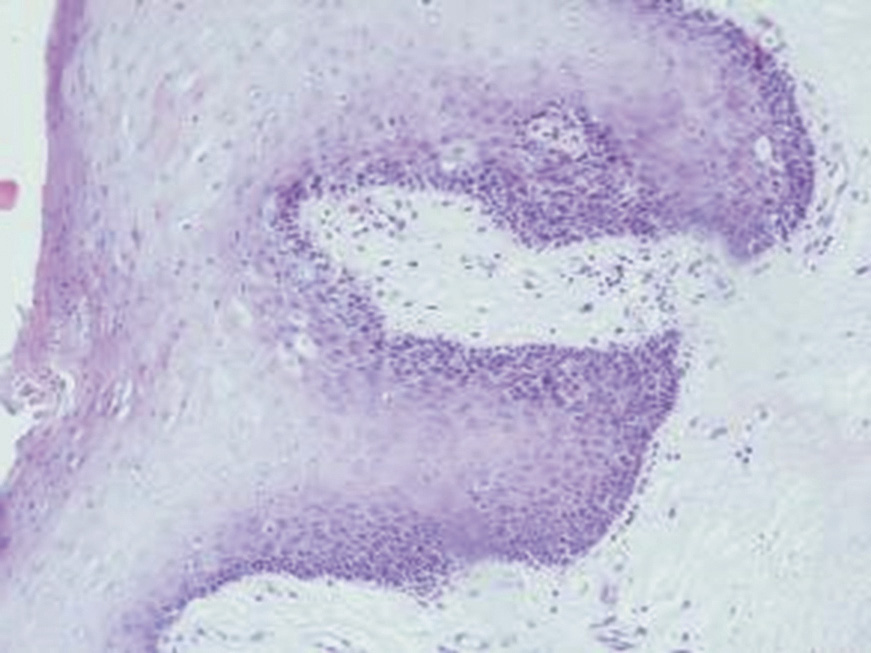

The results of light microscopic evaluation revealed focal hyperplasia of stratified squamous keratinized epithelium with signs of acanthosis, parakeratosis, and hyperkeratosis of varying degrees in all cases (Fig. 1).

Figure 1. Changes of the lip mucosa in a patient of Group A. Focal hyperplasia with acanthosis and hyperorthoceratosis of the squamous epithelium. Staining with hematoxylin and eosin, ×100.

The severity of reactive changes decreased toward the resection line. In the epithelium of the affected lip area in Group A patients, alterations predominantly involved the spinous and granular layers. Some specimens contained balloon-shaped cells resembling koilocytes, with excessive optically clear cytoplasm due to glycogen accumulation. The submucosa exhibited uniformly distributed capillaries with ectatic loops; mild perivascular edema of the interstitium with either no inflammation or focal lymphocytic infiltration of minimal severity.